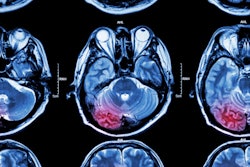

Although ischemic stroke is fairly rare as a cause of dizziness in the ED setting, it can be difficult to discern whether dizziness is caused by nonischemic factors -- a problem that presents a "diagnostic dilemma" for ED clinicians, Tegtmeyer and colleagues noted.

"This dilemma is further hindered by the poor sensitivity of CT and CTA for posterior fossa strokes," they wrote.

Previous research has suggested that MRI offers high sensitivity for detecting posterior fossa strokes, although conventional MRI may not be readily available in all practice settings, the group explained. That's why other imaging strategies such as portable MRI and CT perfusion could help, especially since they may have higher sensitivity than CT/CTA.